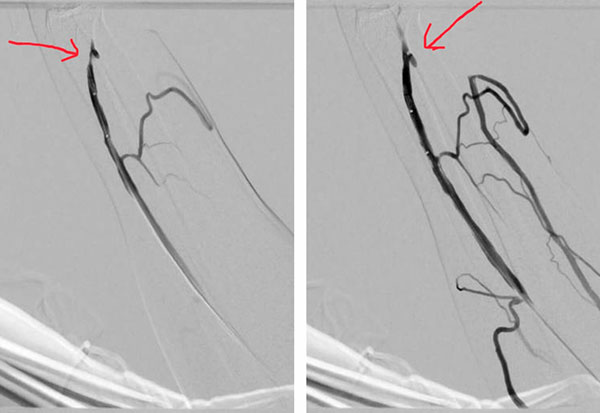

术前 术后

近年来,经皮穿刺球囊成形术(PTA)因其微创、安全、有效的特点已替代外科手术成为动静脉内瘘血管狭窄的首选治疗方法。广东省人民医院肾内科仅2018年为尿毒症患者建立血管通路手术就500多例,其中通过DSA(血管造影)或B超引导下的动静脉内瘘狭窄球囊扩张术就过百例。但DSA引导下的手术需要特定的DSA场所、设备、放射管理操作人员,门槛高,技术要求高,并且对术者有辐射伤害的可能,未能在众多医院中普及,2017年除少数几家三甲医院外,地级市医院及基层医院尚处于起步阶段或空白。